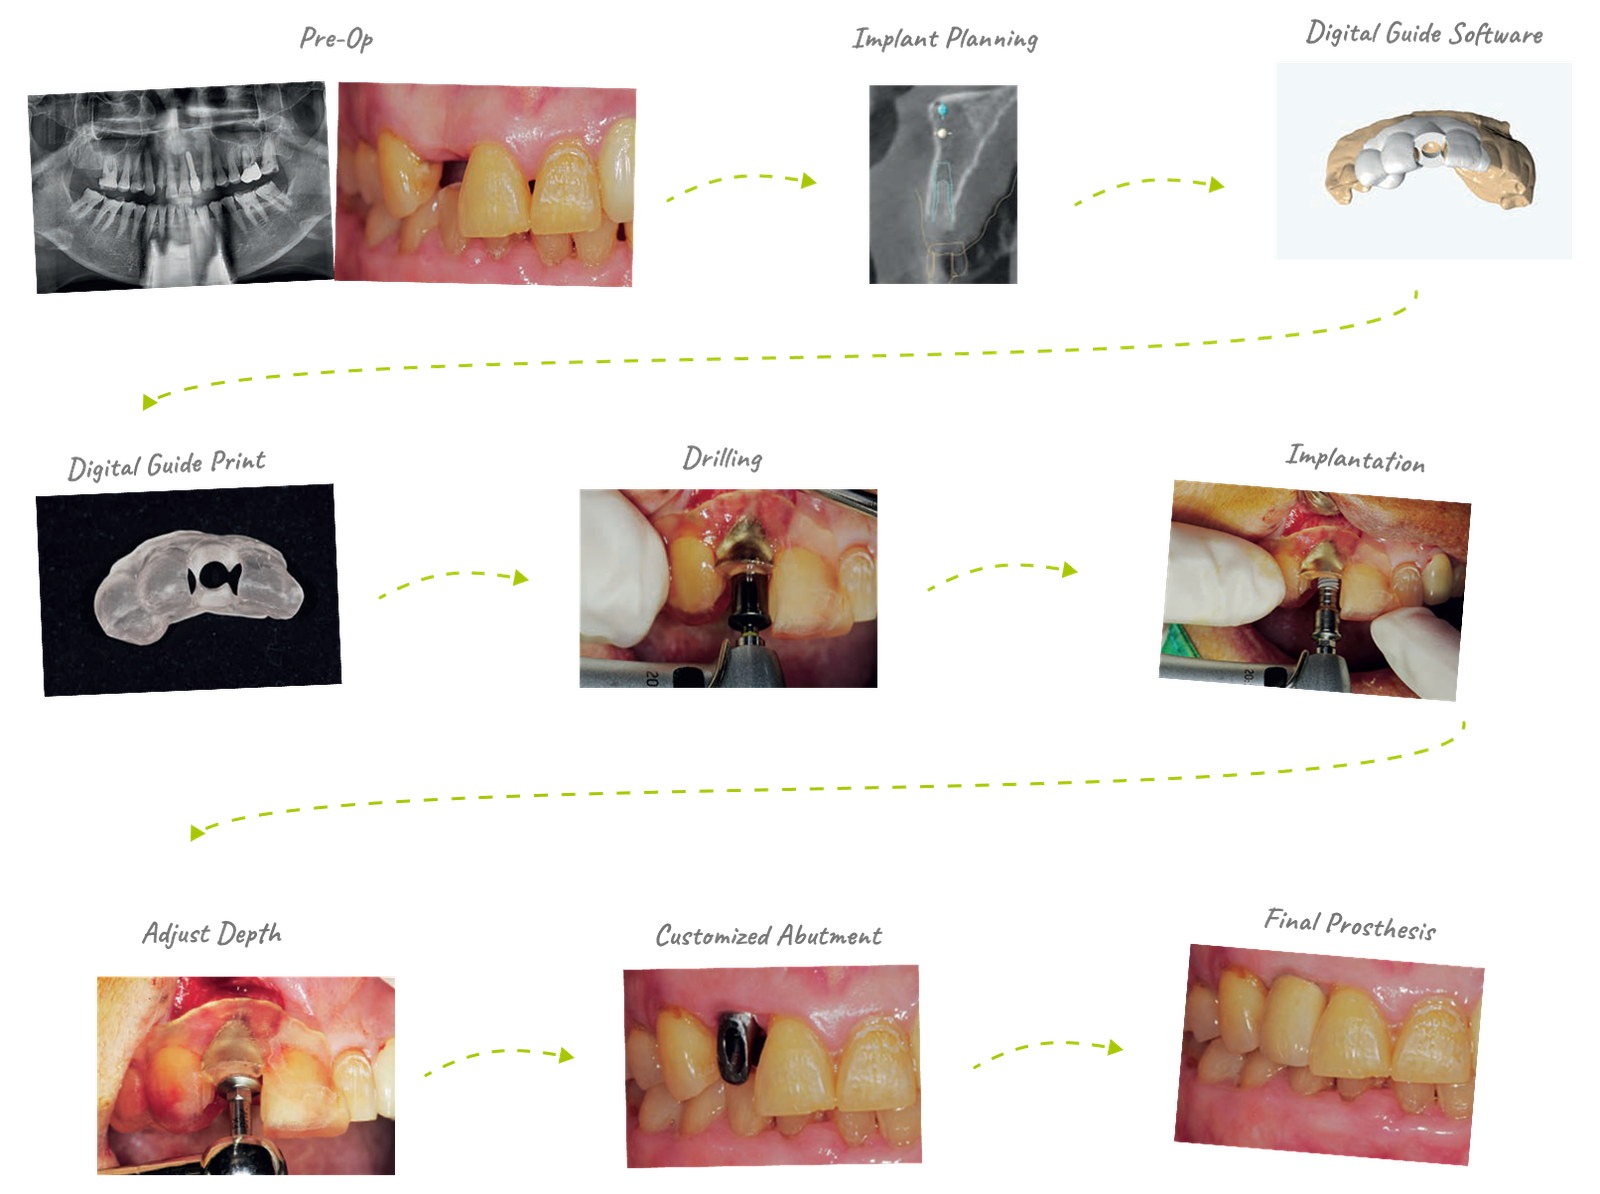

79yrs / Female | Implant Parts #12 | Fix Size: SuperLine 3610 | Guide Kit: Full Kit

It was most often used in anterior implant cases. In the case of anterior teeth, implants need to be placed relatively quickly after tooth extraction for esthetic reasons, but when using a guide, implants can be placed at a planned position and angle without being affected by the shape of the extraction fossa, which is quite satisfactory.

It takes at least one week to produce through a request from the center, but if you design your own using Dentium Digital Guide Software, you can produce it within 30 minutes to an hour. When weeding the guide, pay attention to the ct alignment, and when making the guide, the undercut and border should be well set to fit the patient's mouth. It is recommended to use the anchor pin function for stability.